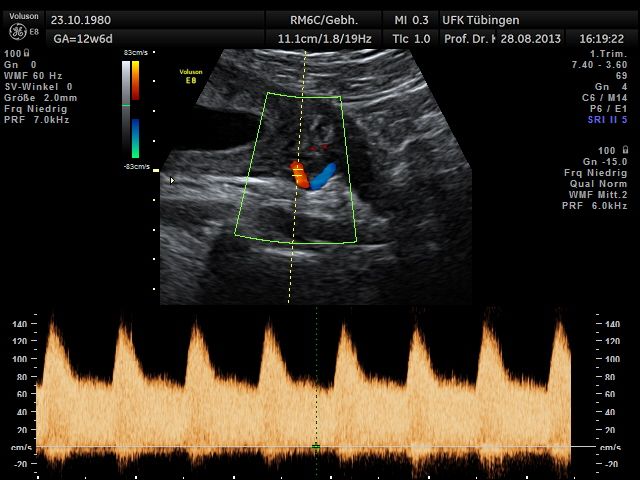

Mithilfe des Ersttrimester-Screenings kann das persönliche Risiko einer Präeklampsie bestimmt werden. Dazu wird die Vorgeschichte der Schwangeren, der aktuelle Blutdruck, das Ergebnis der Ultraschalluntersuchung (Widerstand in den Gebärmutter-nahen Gefäßen) und der Blutabnahme bei Ihnen (PAPP-A) kombiniert. Sollte das Risiko über 1:100 sein, empfehlen wir die tägliche Einnahme von Aspirin 150mg bis zu 35.SSW und eine gezielte Überwachung der weiteren Schwangerschaft.

Das Ergebnis der Ultraschalluntersuchung ist wegweisend. Dabei wird der Fet vermessen, die Organe werden untersucht und die sonographischen Marker zur Risikoberechnung für Chromosomenstörungen werden beurteilt. Das sind: die Nackentransparenzdicke, Nasenbein sowie der Blutfluss in der rechten Herzhälfte und im Ductus venosus, einem Gefäß in der Leber des Feten.